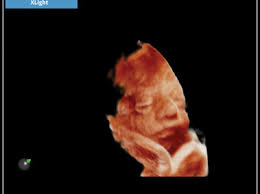

MyLab™X6, au-delà de la flexibilité

Le nouveau MyLab™X6 d'Esaote rend votre flux de travail si efficace et fluide que non seulement il augmente la productivité, mais il dynamise également vos performances cliniques. Le moniteur LED de 21,5” et sa technologie HD IPS délivrent une haute qualité d'image et des examens détaillés. Une réponse rapide et une utilisation facile de l'interface s'adaptent également à tous vos besoins cliniques, offrant confort et flexibilité à vos évaluations.